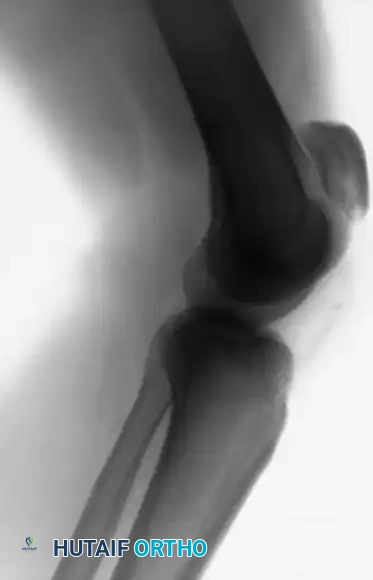

FIGURE 48-29: Degenerative spurring (the "tooth sign") visualized on a tangential view of the patella. This radiographic finding is highly indicative of significant, chronic degenerative changes within the quadriceps mechanism.

Radiographic Evaluation:

Standard anteroposterior (AP) and lateral radiographs are mandatory. A lateral radiograph, particularly with the knee flexed to 30 degrees, is highly sensitive for evaluating patellar height. A superiorly displaced patella (Insall-Salvati ratio > 1.2) confirms a patellar tendon rupture. If the clinical diagnosis remains equivocal due to swelling or patient guarding, ultrasonography or Magnetic Resonance Imaging (MRI) provides definitive visualization of the soft tissue defect.

FIGURE 48-30: Anteroposterior and lateral radiographs demonstrating an acute patellar tendon rupture. Note the significant superior displacement of the patella (patella alta) on the lateral view, caused by the unopposed contraction of the quadriceps muscle.